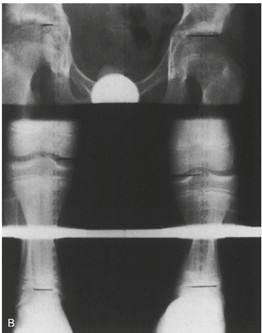

Сканография конечностей

(Взято из Tachdjian`s pediatric orthopaedics, 2 ed., 2022.)